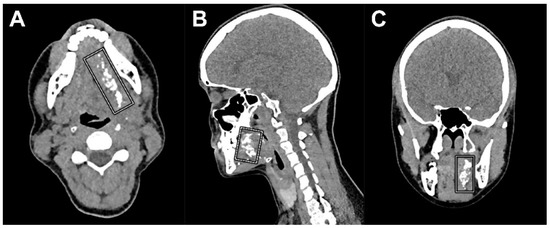

Figure 3.

CT lymphographic images acquired 25 min post-injection of Lipiodol® in the same patient (patient 6). (A) Axial plane, (B) coronal plane, and (C) sagittal plane; (*) injection site. Lymphatic drainage was observed (white arrows), yet no SLNs were identified on CTL in this patient.